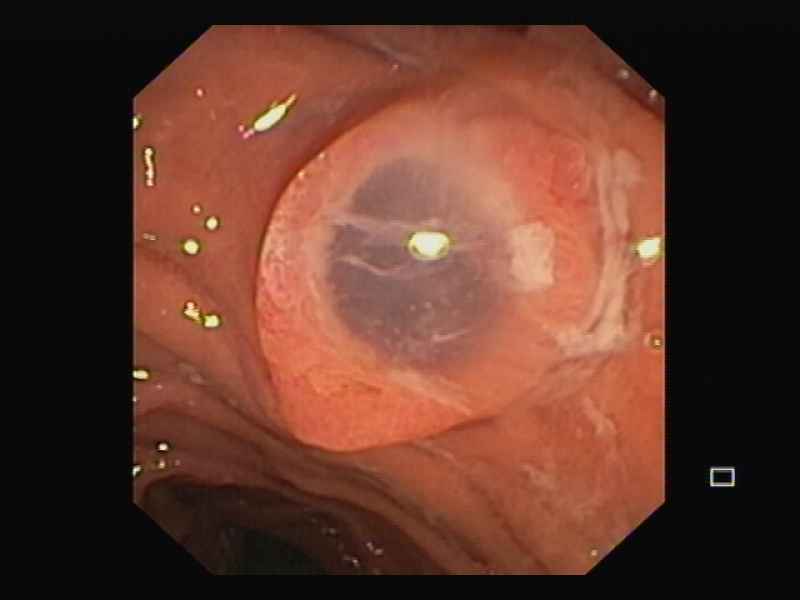

Intraductal Papillary Mucinous Neoplasm of the pancreas with gastric fistula

Fotografia